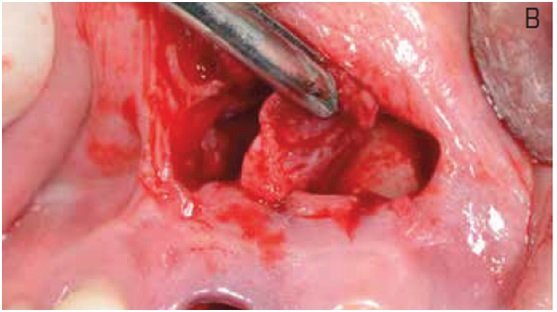

A presença de patologias na região apical de um dente comprometido pode interferir diretamente no tratamento com implantes dentários através da reincidência de infecção, e indiretamente através do trauma necessário para adequada limpeza do sítio infectado. Esse trauma torna-se mais relevante na região anterior maxilar, suscetível à recessão óssea, e recursos que o minimizem estão indicados. Através de um caso clínico, o presente trabalho apresenta o tratamento de uma lesão extensa na região periapical de um incisivo central maxilar com comprometimento da tábua óssea vestibular na região apical.

O tratamento consistiu na extração atraumática do dente e incisão de acesso na região periapical, para facilitar o procedimento de debridamento e minimizar o trauma mecânico na região cervical. Após remoção superficial do osso infectado e curetagem da região, um implante foi imediatamente instalado e a região apical foi preenchida com hidroxiapatita sintética para recuperar o volume perdido. No mesmo dia, uma provisória apoiada nos dentes adjacentes foi instalada e, após cinco meses, o paciente recebeu tratamento protético definitivo. Considerações sobre aspectos teóricos e práticos do procedimento são apresentadas e discutidas, com ênfase na previsibilidade estética do tratamento.